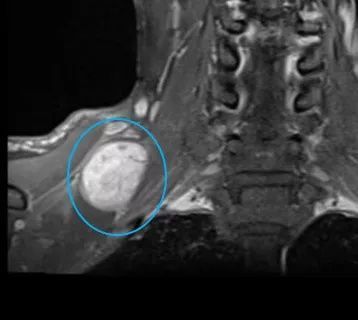

张先生和赵先生住院以后都做了颈部的磁共振检查,检查结果显示张先生的肿块长在了下颌角的边上,肿块还包绕着颈部的大血管。而赵先生的肿块是从臂丛神经上长出来的。

赵先生颈部磁共振 医院供图